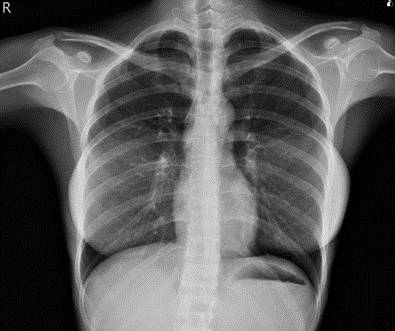

圖二、肺部電腦斷層之橫切狀面(Axial  view)。

雙側肺部上肺葉呈現毛玻璃樣的變化(橘色箭頭),雙側肺部底部呈現廣泛性浸潤(紅色圈圈)。

肺部電腦斷層,兩個主要的病灶:

1.雙側肺部底部呈現廣泛性浸潤,可見於airbronchogram sign(紅色圈圈),代表實質化的病變(consolidation),鑑別診斷包含肺炎與肺水腫。

複習:airbronchogram sign指出“支氣管和肺泡內充滿空氣”,遠端支氣管在一般影像上是不容易辨識,當鄰近肺泡組織被其他物質填滿(如滲透液、水或血),因而被呈現出來。

2.雙側肺部上肺葉呈現許多毛玻璃樣的變化(ground glass opacity) (橘紅色箭頭),呈現片狀或是也有擴散狀分佈。

此外,肺部沒有明顯腫瘤狀的病灶,肺部肺動脈血管也沒有栓塞的情況。